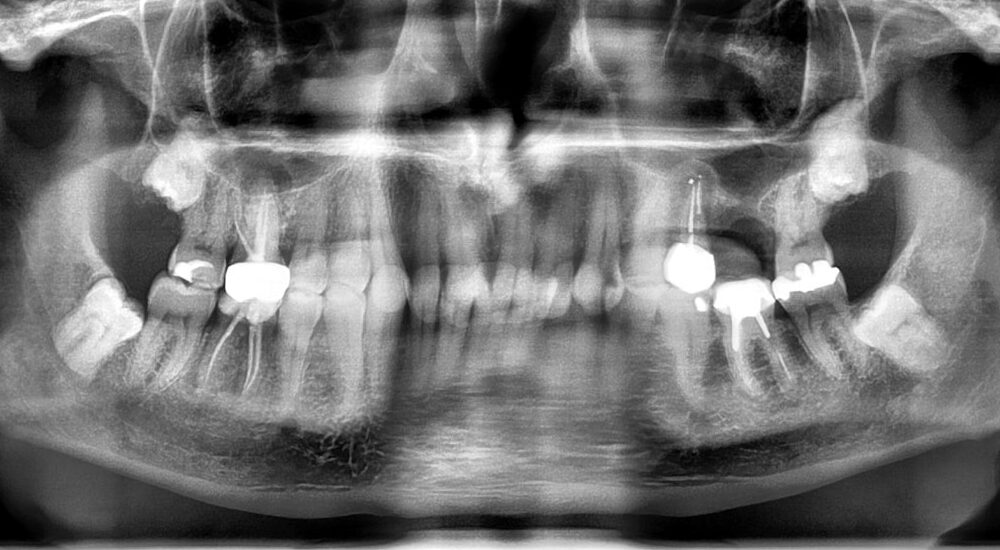

Etant un omnipraticien comme beaucoup, cet exposé est simplement un partage de mon expérience d’une dentisterie réaliste au quotidien. Ce cas présente la réalisation d’un Onlay sur la 26, en 2003 et d’une coiffe sur la 25 ; (Fig.1). Les deux pièces prothétiques ont été fabriquées en vitrocéramique (Empress 2 Ivoclar Vivadent). On constate une fracture de la 26, douze ans après la pose (la 25 est intacte). L’origine de la fracture est essentiellement occlusale. En effet la patiente a perdu la 27 qui a été remplacée par un implant. Il faut noter qu’elle est restée édentée pendant les 6 mois de temporisation. Cette patiente a des problèmes d’occlusion comme on peut le constater en regardant la face occlusale de la 24 qui présente des facettes d’usures importantes. Ce cas vous montre le devenir d’une restauration adhésive sur dent pulpée à long terme : la dent est toujours vivante....